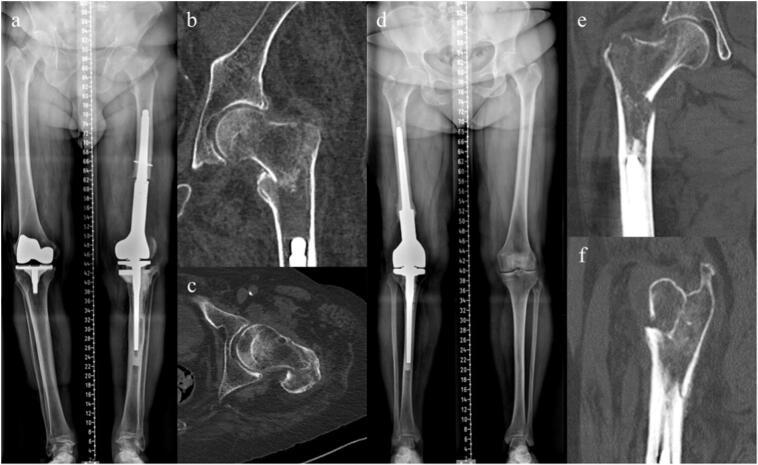

The incidence of periprosthetic fractures is increasing, presenting significant challenges due to patient longevity and the complexity of repeated surgeries. This report details the successful treatment of a previously unreported periprosthetic fracture pattern using a modified dynamic hip screw (DHS) technique. Two cases involved patients with extracapsular fractures in short proximal femur segments above megaprostheses. The fractures were reduced and stabilized with a DHS device, complemented by 3.5 mm screws from a different manufacturer to achieve effective bicortical fixation around the thick stems. Early weight-bearing was initiated postoperatively, with both patients achieving fracture healing without mechanical complications. This approach highlights the importance of careful preoperative planning and the selection of appropriate fixation methods, particularly in complex cases where traditional solutions may not be viable.